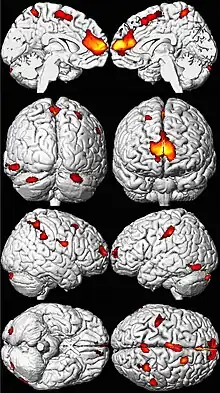

.png.webp)

Lead poisoning can cause a variety of symptoms and signs which vary depending on the individual and the duration of lead exposure.[27][28] Symptoms are nonspecific and may be subtle, and someone with elevated lead levels may have no symptoms.[29] Symptoms usually develop over weeks to months as lead builds up in the body during a chronic exposure, but acute symptoms from brief, intense exposures also occur.[30] Symptoms from exposure to organic lead, which is probably more toxic than inorganic lead due to its lipid solubility, occur rapidly.[31] Poisoning by organic lead compounds has symptoms predominantly in the central nervous system, such as insomnia, delirium, cognitive deficits, tremor, hallucinations, and convulsions.[26]

Lead exposure in children is also correlated with neuropsychiatric disorders such as attention deficit hyperactivity disorder and anti-social behaviour.[76] Elevated lead levels in children are correlated with higher scores on aggression and delinquency measures.[5] A correlation has also been found between prenatal and early childhood lead exposure and violent crime in adulthood.[72] Countries with the highest air lead levels have also been found to have the highest murder rates, after adjusting for confounding factors.[5] A May 2000 study by economic consultant Rick Nevin theorizes that lead exposure explains 65% to 90% of the variation in violent crime rates in the US.[83][84] A 2007 paper by the same author claims to show a strong association between preschool blood lead and subsequent crime rate trends over several decades across nine countries.[85][86] Lead exposure in childhood appears to increase school suspensions and juvenile detention among boys.[87] It is believed that the U.S. ban on lead paint in buildings in the late 1970s, as well as the phaseout of leaded gasoline in the 1970s and 1980s, partially helped contribute to the decline of violent crime in the United States since the early 1990s.[86]

Neuroanatomical pathology due to lead exposure is more pronounced in males, suggesting that lead-related toxicity has a disparate impact across sexes.[74]